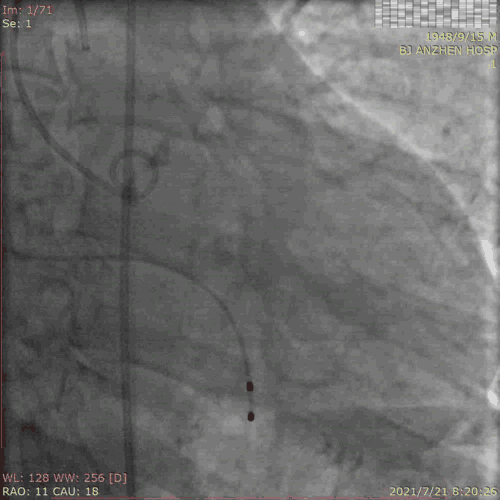

TAVR过程:患者局麻后,植入临时起搏器,穿右股动脉送入23mm球囊预扩张病变,左、右冠状动脉未受明显影响,决定直接植入爱德华SAPIEN 3 26mm 球扩式瓣膜,选择标准位进行释放。